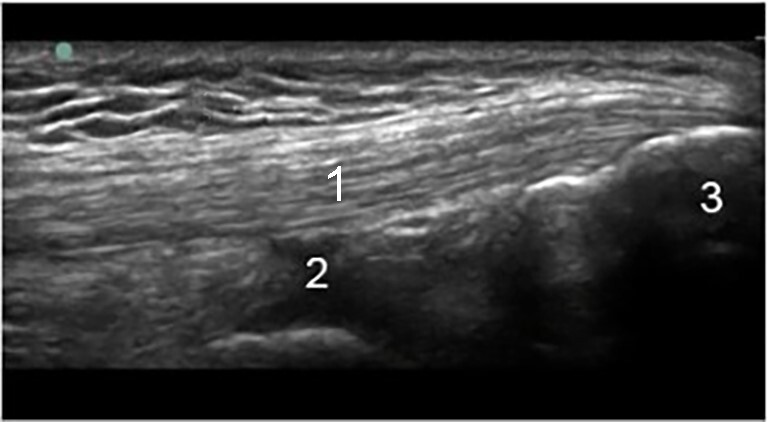

Rodilla: Fosa suprarrotuliana - Imagen

Tendón del cuádriceps

Receso suprapatelar

Rótula